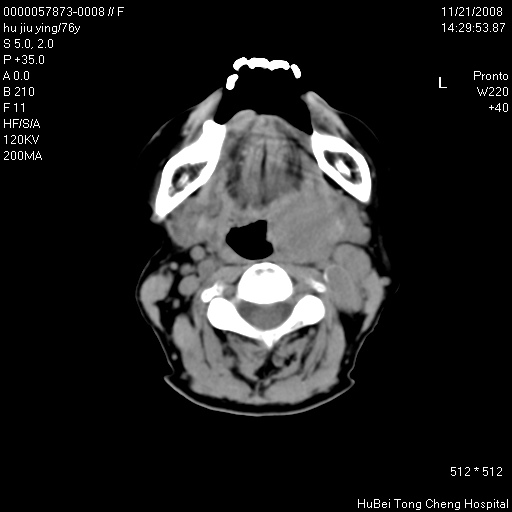

患者 女,76岁。左颈部包块20余天。pe:左侧扁桃体ⅲ度肿大,表面不平,有新生血管,右咽柱红肿,无溃疡。左颈上部包块约3cm×4cm大小,质中等,压痛,边界不清,不能移动。

临床诊断:左侧扁桃体肿瘤?

咽部及颈部ct轴位平扫(层厚、层距均为5mm),图像如下:

左侧咽旁软组织密度肿块影,形态不规则,与周围结构分界欠清,性质待定,建议增强;另双侧上颌窦炎.